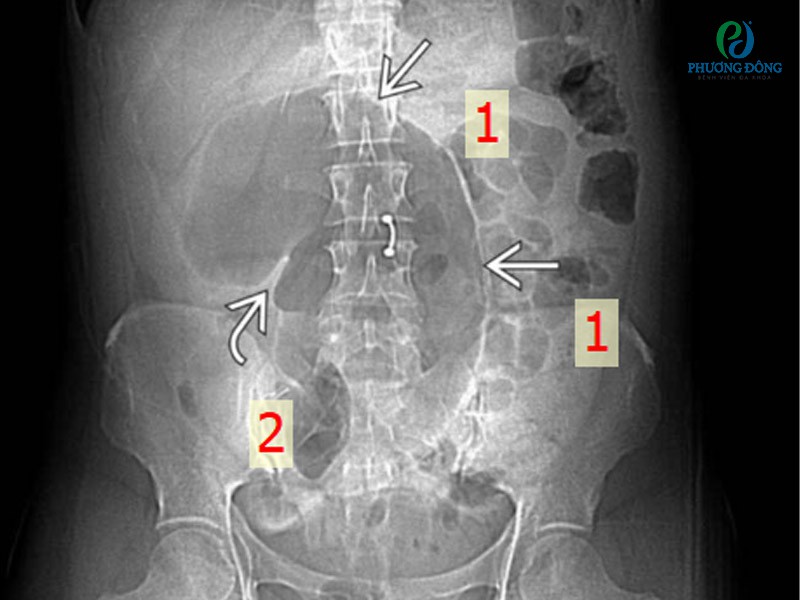

Xoắn manh tràng trên X–quangXoắn manh tràng trên X–quang

Ghi chú: Phim chụp X-quang tư thế nằm ngửa cho thấy một đoạn ruột (manh tràng) căng phồng do khí (mũi tên 1) nằm giữa bụng. Đáy manh tràng hướng về góc phần tư trên, và van hồi manh tràng (mũi tên 2) hướng sang bên. Ruột non căng phồng do khí, trong khi đại tràng trái tương đối xẹp.